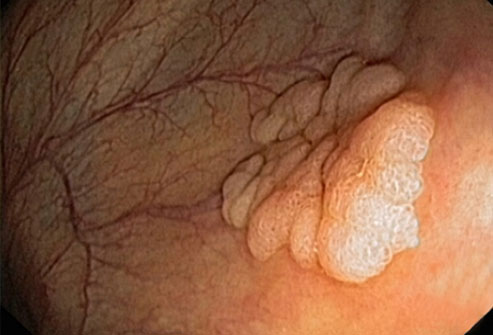

宫颈癌

通过常规宫颈涂片,宫颈癌(如图)很容易预防。宫颈是子宫和阴道之间的狭窄通道。宫颈涂片能发现宫颈上的异常细胞,并将它们在癌变前移除。宫颈癌的主要原因是人类乳头瘤病毒(HPV),一种性传播感染。